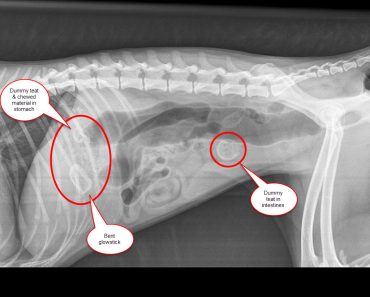

Once at PDSA, X-rays revealed a potentially fatal blockage in her intestine and several other items in Rosie’s stomach. PDSA Vet Nigel Crane explained: “Dogs often use their mouth to investigate objects, and sometimes swallow things by mistake. Although objects sometimes pass through without harm, some get stuck in the dog’s stomach or intestines, which is extremely dangerous and can be life-threating.”

Poor Rosie was already very weak when she arrived at the hospital and vets were uncertain whether she would survive an emergency operation. But it was her only chance of survival. Vets were shocked when they removed the items and realised what they were – the dummy teats had clearly been inside her for some time.